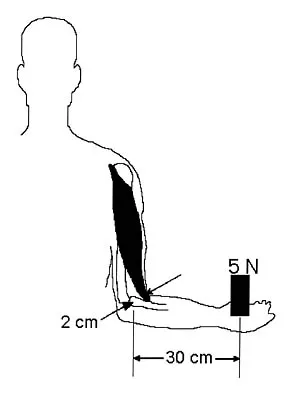

The brachialis muscle is innervated by what two nerves?

Explanation